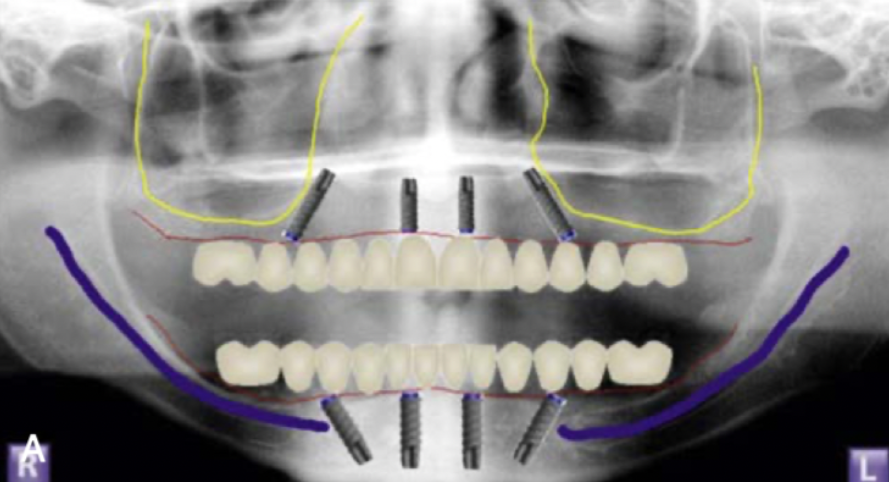

대부분 앞쪽에는 뼈가 있어서

틀니 오래 끼신 분도

이렇게 기존에서 심으면 가능한 경우가 많아요

더군다나 디지털 가이드를 이용해서

뼈가 얇은 경우에도 정확하게 심을 수 있어요